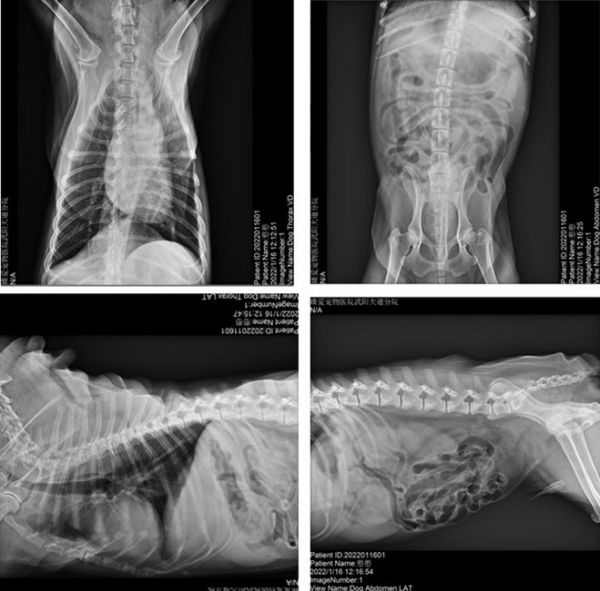

4.3 DR检查

图4. DR图片

DR检查结果:肋骨可见钙化灶,肠道积气。其他未见明显异常。